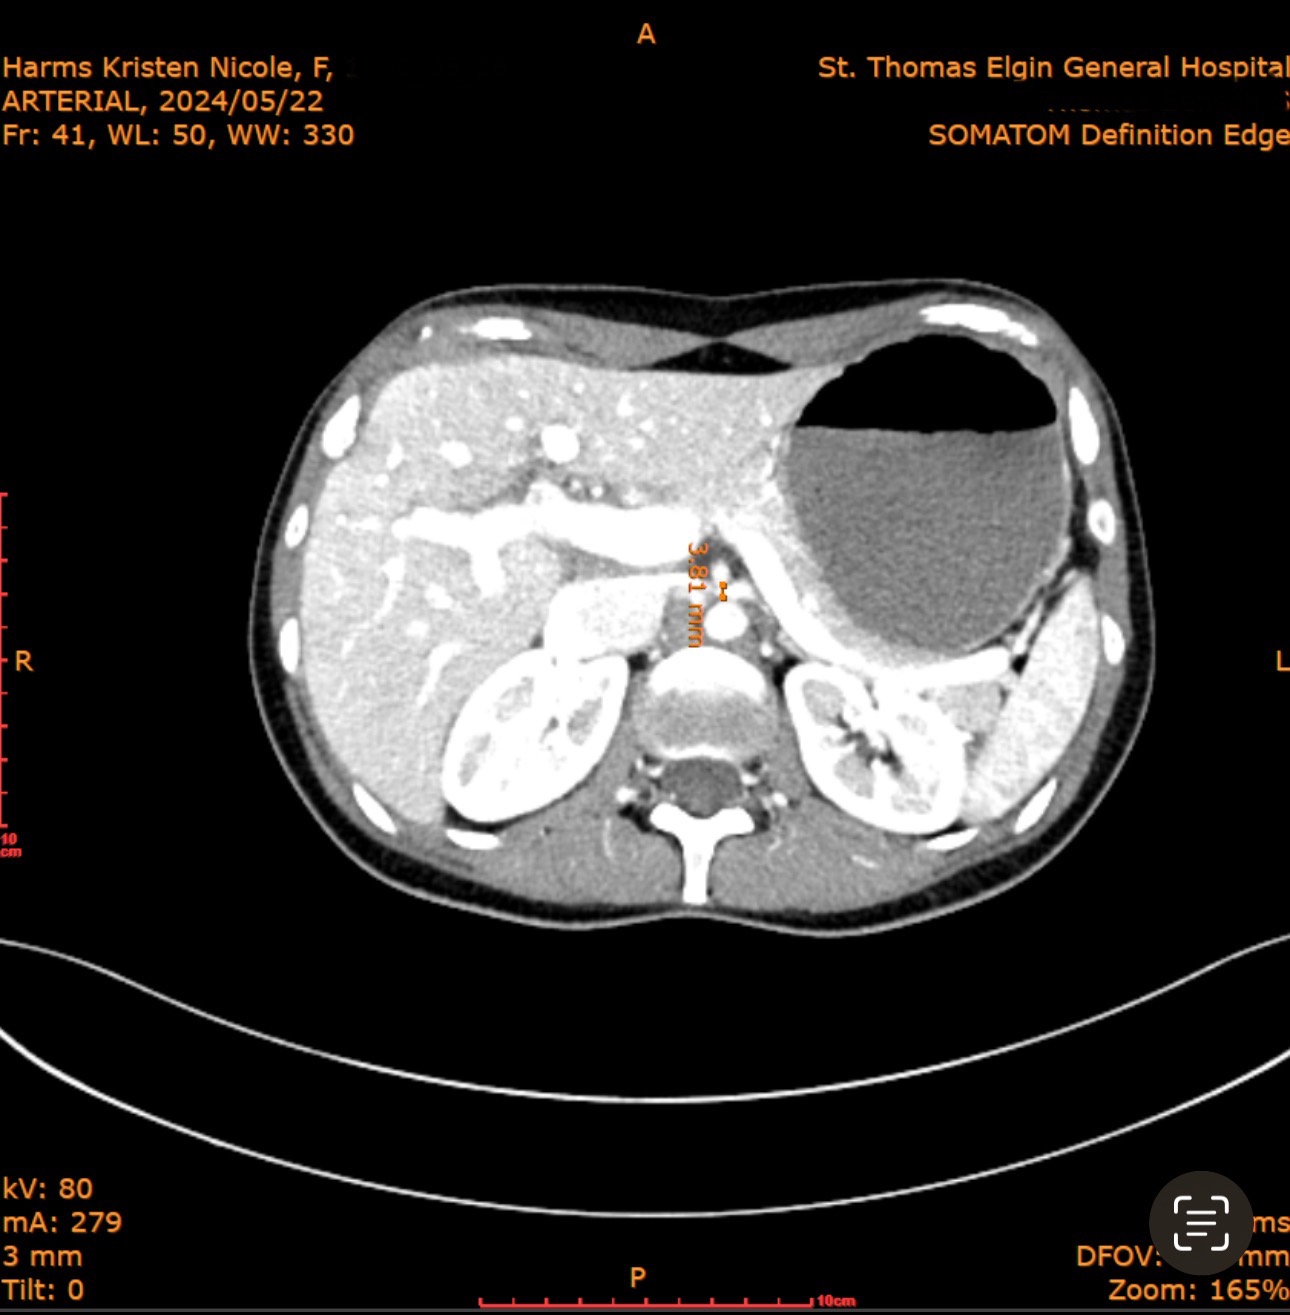

I was recently diagnosed with several rare vascular compression syndromes after years of misdiagnosis’s and progressing symptoms, including Superior Mesenteric Artery Syndrome (SMAS), May-Thurner Syndrome, and Nutcracker Syndrome. These conditions severely restrict blood flow to my digestive organs and block part of my duodenum, causing constant pain, extreme weight loss, and severe malnutrition. Despite trying every medical option available in Canada, I’ve been unable to access the life-saving surgery I need in a reasonable timeframe. Currently in Canada, there is only one surgical option that does not fix the compression and has an 80% failure rate. My doctor has been unable to find a surgeon even willing to treat SMAS as all claim it is too difficult to deal with and it is an extremely rare disorder. I have went from 161lbs, down to 100lbs, with severe gastro symptoms daily and constant pain, nausea and vomiting. I receive infusions for my iron, frequent b12 injections and high doses of vitamin d to try and keep my levels up as my malabsorption is so severe causing anemia. The SMAS causes food and acid to backup into my stomach, which has caused bad, long term gastritis. My body has been in ketosis long term as I am starving despite still maintaining adequate calories, I have muscle wasting, and severe fatigue along with many secondary complications from the SMAS. This has completely taken away my quality of life, and I am now suffering without any help in Canada for this condition.

SMAS can be fatal when left untreated. After extensive research and consultation, I have made plans to be treated by Dr. Alvear in the Philippines, who specializes in treating Superior Mesenteric Artery Syndrome. The surgery and recovery plan he offers provide the best chance for me to regain my health, nutrition, and quality of life. The procedure I am having done is known as the Alvear procedure. Unlike older surgeries that create a bypass and often fail long term, this procedure fixes the root cause by repositioning and freeing the duodenum (the first part of the small intestine) from the artery compression. The intestine is then moved to a healthier position on the right side of the abdomen to prevent future twisting or obstruction. The result is a restored normal digestive pathway, allowing patients to absorb nutrients and eat again without pain or fear.